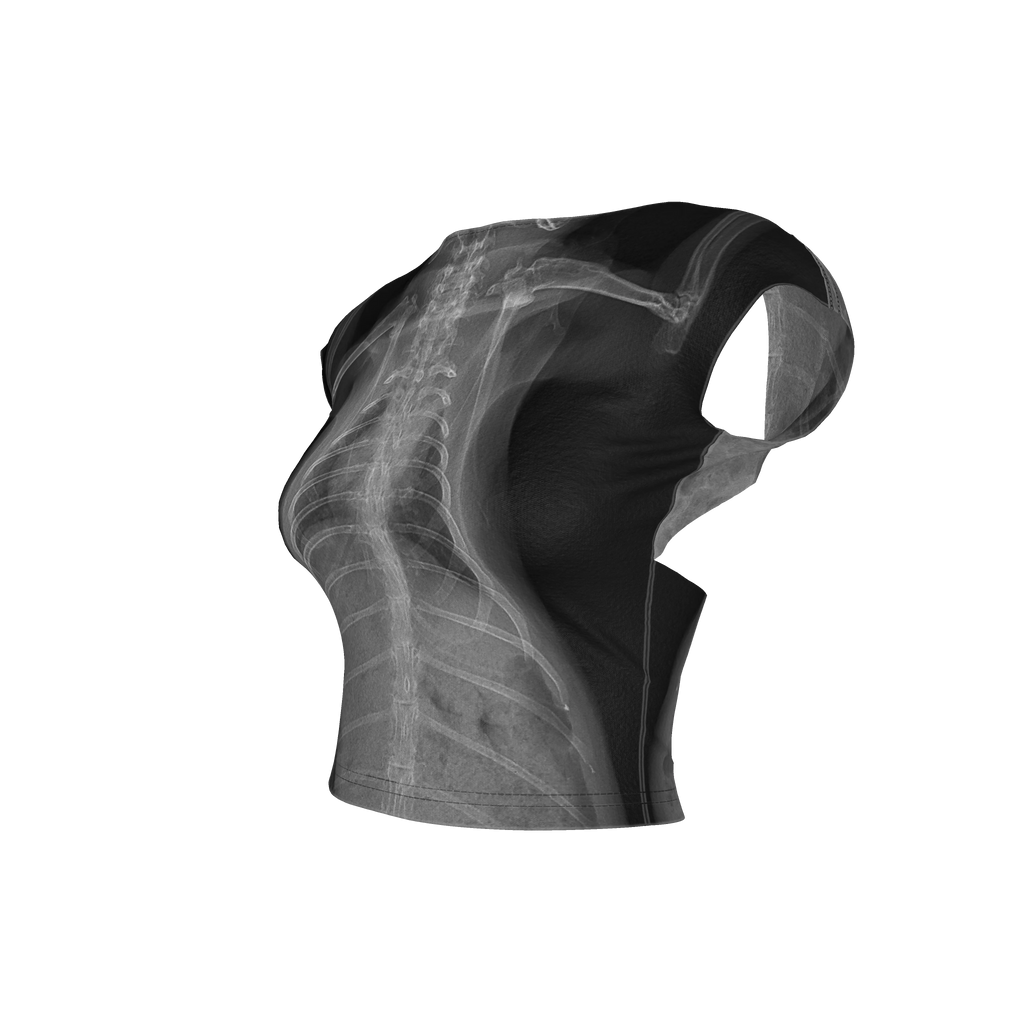

Toll of Love Backless Top

My pet rabbit had a health crisis earlier this year and needed intensive care. It was a long night at the hospital, but she is doing well. Her X-rays were a beautiful thing to come out of a horrible night and I made this outfit to transform those memories into something beautiful.